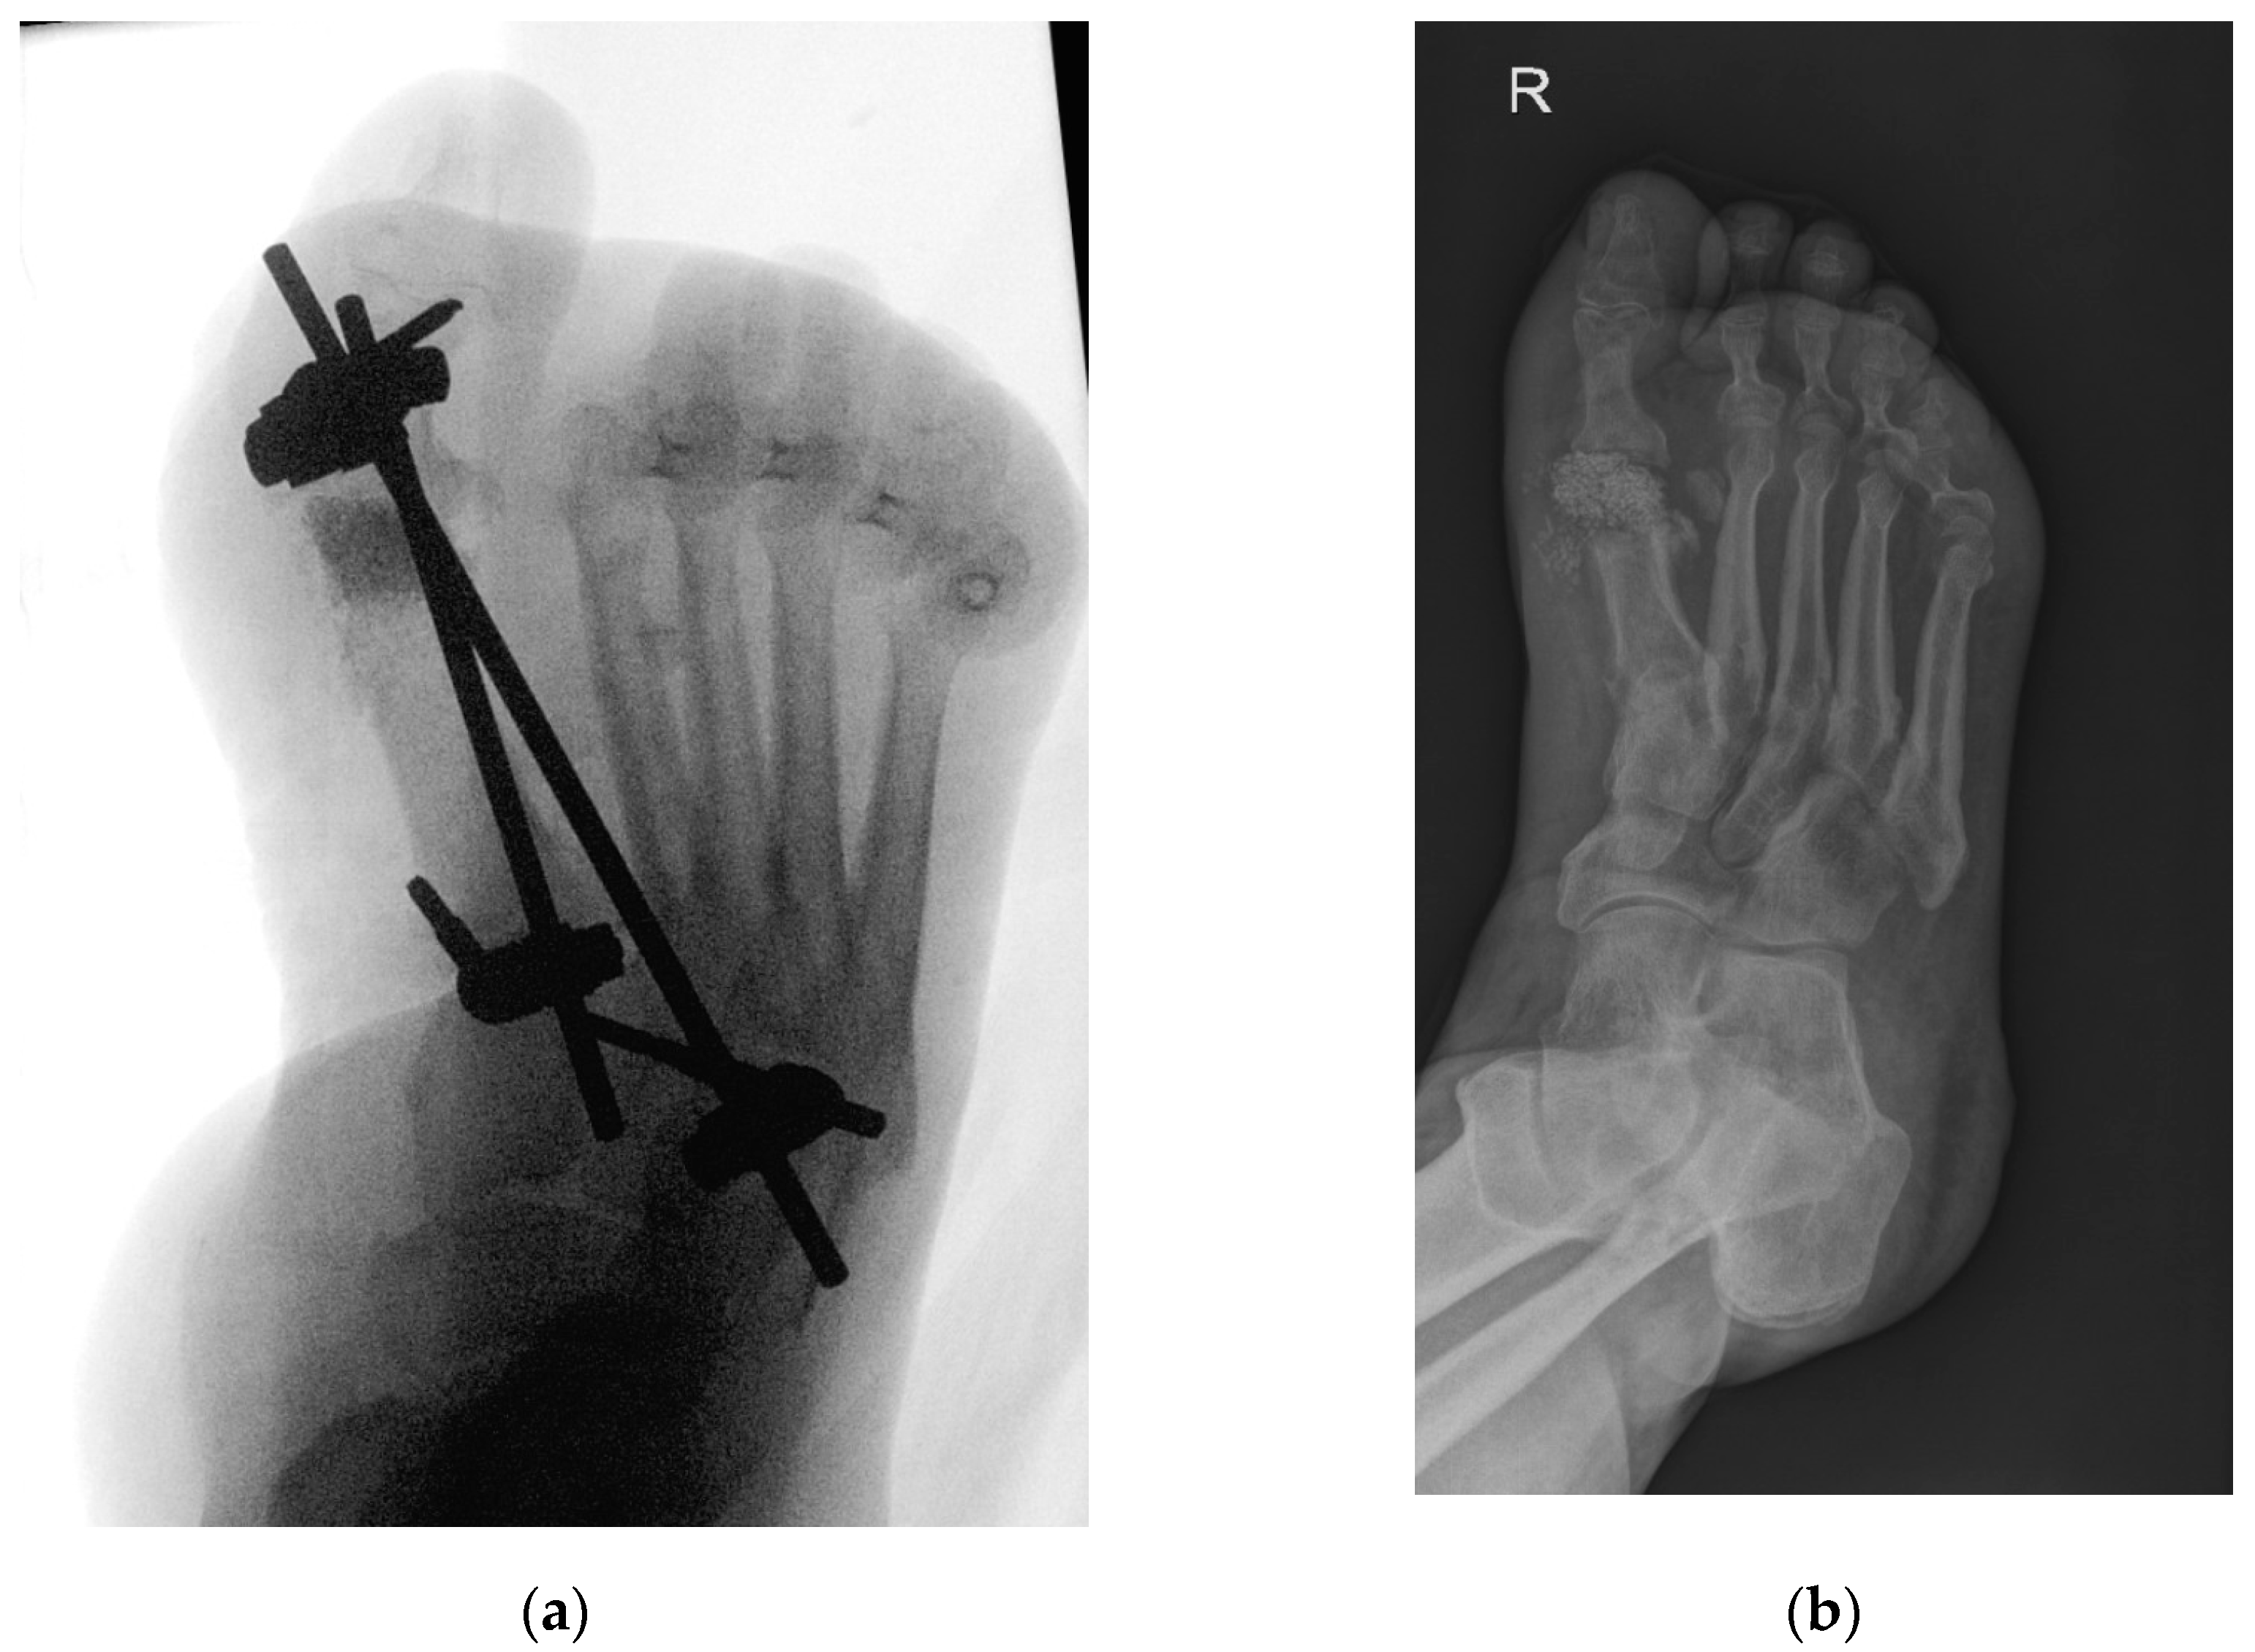

Out of the eight cases included in this group, four were reported to have Charcot neuroarthropathy, and all had clinically and radiologically suspected osteoarthritis. Table 1 shows their detailed characteristics, including significant concomitant diseases documented. For seven patients, the affected site was the first MTP joint, while one patient suffered from osteoarthritis of the lesser (fourth and fifth) MTP joint. Figure 1 demonstrates the intraoperative placement of BAG as well as a small fixator, and the extent of bone defect, remodeling, and osteointegration after three months. Two procedures performed for the treatment of the first MTP joint were single-phase with resection and application of BAG, while five were multiple-phase procedures, with the utilization of antibiotic gentamycin beads (Septopal® Chain, Zimmer Biomet Deutschland GmbH, Freiburg im Breisgau, Germany) in three cases. An external fixator device was used in all seven cases involving the first MTP joint, with removal scheduled after approximately three months. The procedure performed for lesser MTP joint osteoarthritis was single-phase with resection and BAG application, without the use of an external fixator device. All patients received a prolonged antibiotic regime of at least six weeks, with an initial treatment of approximately two weeks of intravenous antibiotic therapy in-hospital. None required revision during the 30-day period postoperation, suffered early complications, or required amputation during the follow-up period. The patient with affected fourth and fifth MTP joints had no early complications and achieved healing; however, as the follow-up period in this case was the shortest (only two months), late complications could not be definitively assessed.

Figure 1.

(a) Intraoperative X-ray—resection of 1st metatarsophalangeal joint, placement of bioactive glass granules, and placement of external fixation device. Image captured intraoperatively with diascopy using Siemens Cios Alpha® (Siemens, Munich, Germany) (average exposition parameters: 50 kV, 0.05 mAs, and 5 fps); (b) patient three months after resection of 1st metatarsophalangeal joint and bioactive glass insertion. Image captured with Philips Digital Diagnost® (Philips, Amsterdam, The Netherlands) (exposure parameters: 70 kV and 2 mAs).